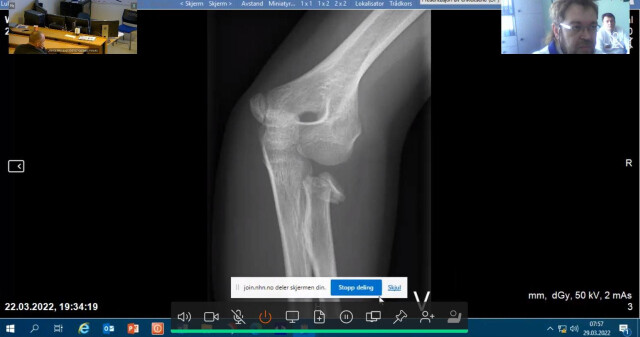

На запрошення колег із Oslo University hospital Ulleval (м. Осло, Норвегія) 29 березня 2022 року співробітники кафедри дитячої хірургії з травматологією та ортопедією Полтавського державного медичного університету та лікарі ортопеди-травматологи КП «І-а МКЛ Полтавської міської ради» взяли участь у клінічному диспуті у режимі онлайн.